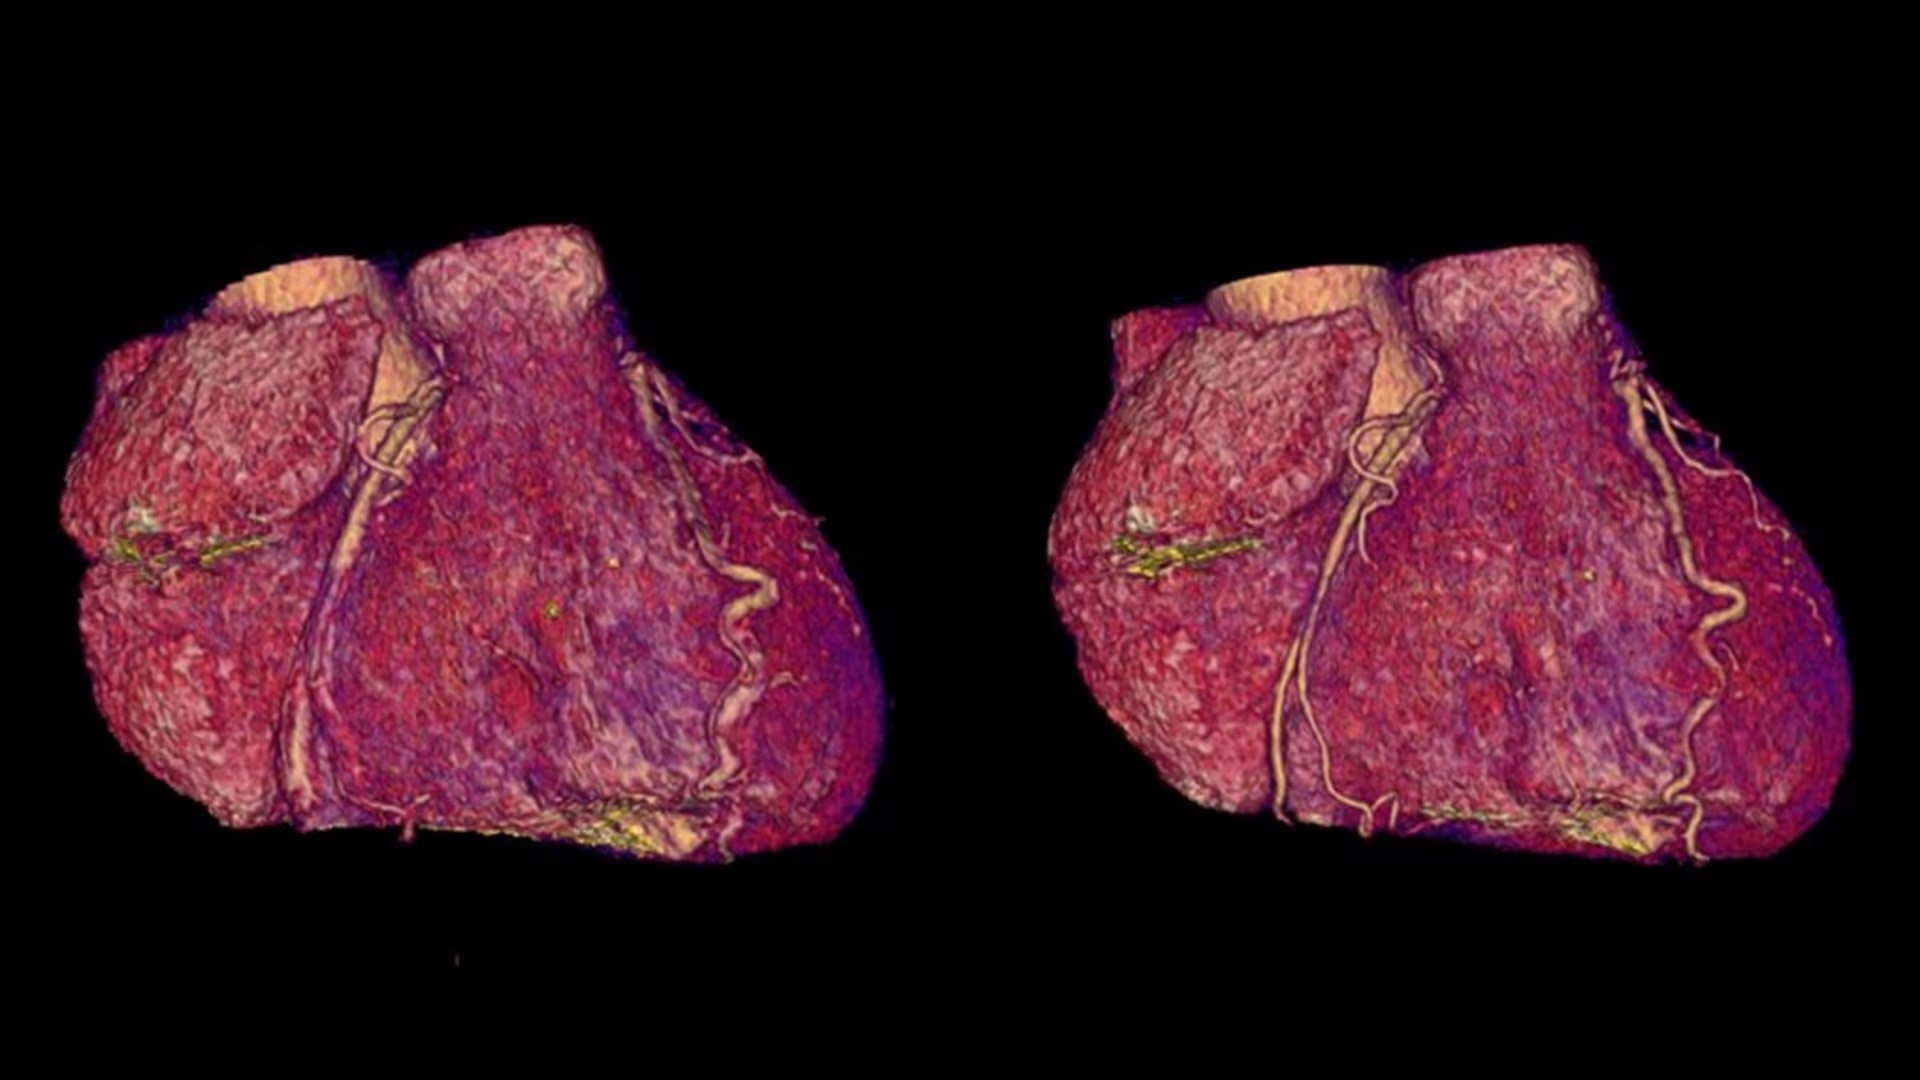

SnapShot Freeze 2

Intelligent and automated whole-heart motion correction for enhanced Cardiac CT imaging.

Automated

Whole-heart motion correction